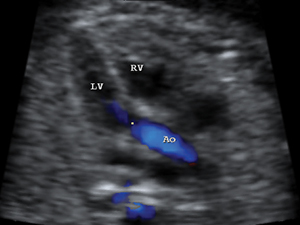

Aortic outflow tract with colour indicating the flow

Colour flow of both pulmonary artery and aorta Limps